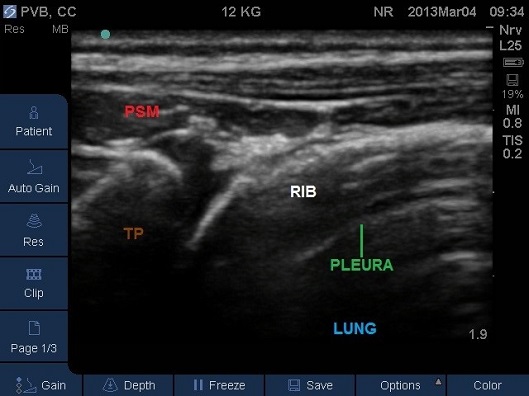

- Identify the pleura beneath (Fig 10). For the best view and a successful block you should ensure the pleura is visible as a bright white solid line with characteristic appearance of intercostal muscles above.

Fig 10. Transverse Plane Mid-Thoracic level. ICM – internal intercostal membrane, PSM – paraspinal muscles, PVS – paravertebral space, TP – tip of transverse process. Note the internal intercostal membrane is continuous with the costotransverse membrane.